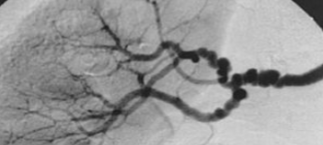

The appearance of these vessels are similar to what?

What is the name of this pathology if renal artery stenosis is secondary to it?

Beads

Fibromuscular dysplasia